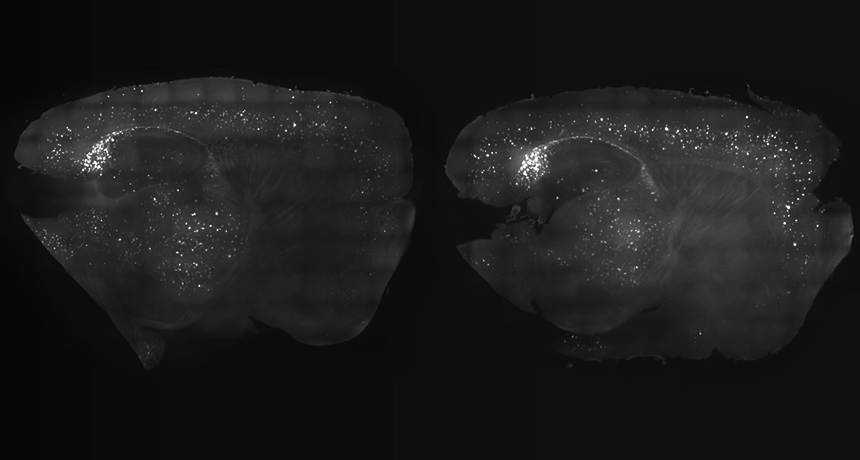

DISAPPERING ACT  Precisely timed lights and sounds reduced amyloid-beta plaques in a mouse brain (left) compared with the brain of a mouse that didn’t receive the treatment (right).